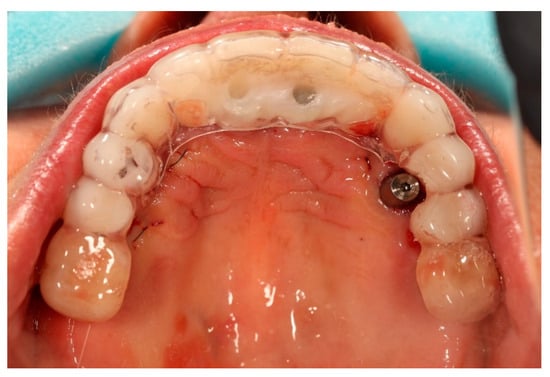

Scanbody SmartFlags® (Apollo Implants Components GmbH, Pforzheim, Germany) were mounted to the multi-unit abutments, and an intraoral digital impression of both arches was obtained using an intraoral Dexis scanner (Figure 5). After scanning, the SmartFlags® and multi-unit abutments were removed from four ICX implants, and the original restorations were reassembled. The newly placed ICX active implants were left with multiunit abutments and secured with corresponding healing caps.

Figure 5. Apollo® scan flags mounted on the multi-unit abutments in the maxilla prior to intraoral digital impression.